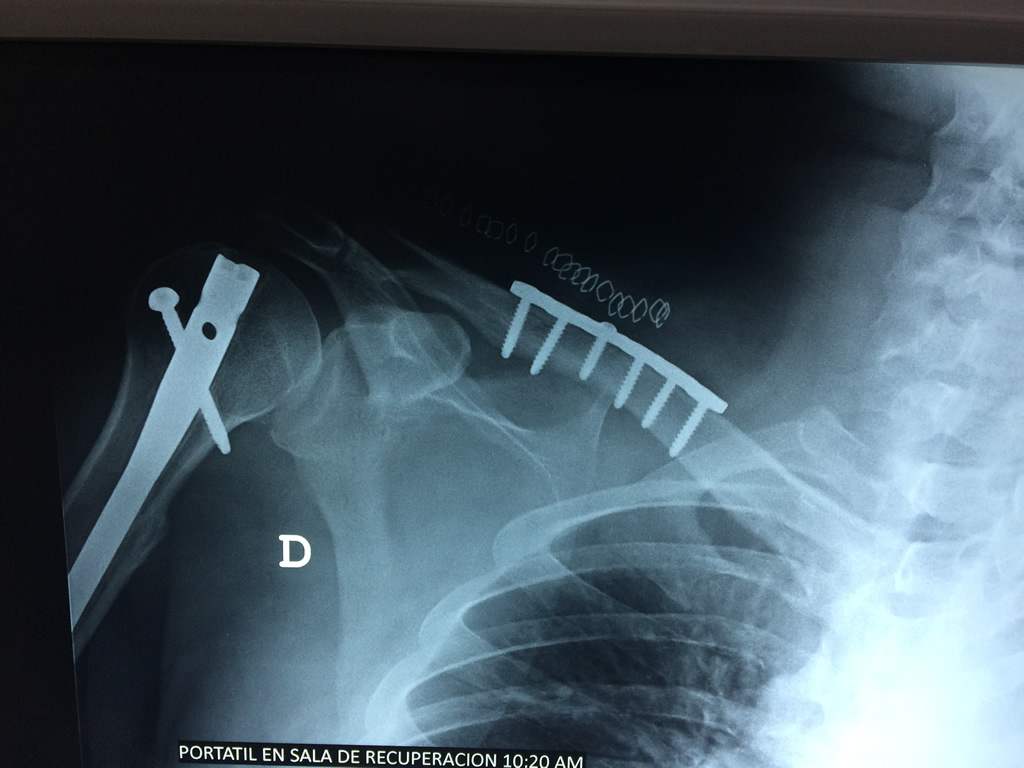

Cirugías de Hombros - Clavícula